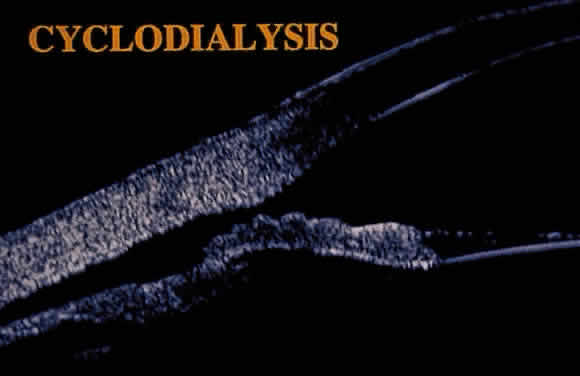

HYPOTONY

Hypotony (i.e., IOP less than 6 mmHg) after glaucoma surgery can result from excessive aqueous outflow (related to excessive filtration [see later], wound leak, or cyclodialysis cleft) or to reduced aqueous production (related to ciliochoroidal detachment, inflammation, inadvertent use of aqueous suppressants, or extensive cyclodestruction).9 These conditions can coexist. For example, low IOP from overfiltration can induce ciliochoroidal detachment and secondary decreased aqueous production. Possible complications include flat anterior chamber, gradual failure of the bleb, visual loss, cataract, corneal edema, Descemet's membrane folds, choroidal hemorrhage, macular and optic disc edema, and chorioretinal folds (predominantly in young myopic patients). According to Spaeth (Table 1),10 the severity of flat anterior chamber can be classified as grade I when there is peripheral-iris apposition, grade II with pupillary border-corneal apposition, or grade III with lens-corneal touch (see Chapter 15). The central anterior chamber depth also can be described relative to the corneal thickness. Choroidal effusion occurs when fluid collects in the suprachoroidal space (Fig. 2), resulting in forward movement of the lens iris diaphragm with anterior chamber shallowing. On fundus examination, moundlike elevations of the choroid, more commonly in the periphery, are visible.